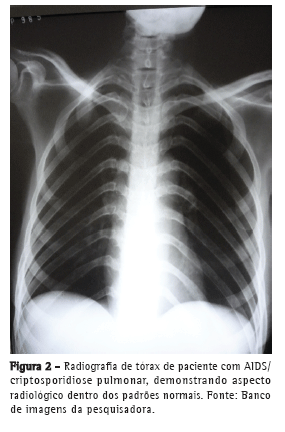

As manifestações clínicas da criptosporidiose pulmonar são inespecíficas e incluem habitualmente tosse crônica, febre e dispneia como sintomas mais frequentes, podendo ou não apresentar alterações radiológicas.(2) Apesar de não haver descrição de achado radiológico patognomônico de criptosporidiose pulmonar, tem sido descrita a presença de opacidade intersticial em alguns relatos de casos.(2,3,7,8)

Em uma pesquisa conduzida em hospitais de referência para atendimento de pacientes com HIV/AIDS e suspeita clínica de tuberculose pulmonar em Recife (PE), de um total de 130 exames de escarro realizados até o momento, Cryptosporidium spp. foi o único agente identificado em 2 (1,5%) daqueles pacientes; o diagnóstico foi realizado através da identificação de oocistos de Cryptosporidium spp. no exame de escarro corado com Ziehl-Neelsen (Figura 1). Em ambos os casos, os pacientes apresentaram febre vespertina, tosse, perda ponderal e mal-estar geral, sugerindo o diagnóstico de tuberculose pulmonar. Nos 2 casos estudados observou-se um grave comprometimento imune, com contagem das células T CD4 muito baixas (25 e 37células/µL). Apesar de não ter sido pesquisada a presença de Pneumocystis jirovecii, foi prescrito sulfametoxazol/trimetoprima para a profilaxia contra esse agente. Ambos os pacientes tiveram diagnóstico recente de AIDS, e apenas 1 deles teve suspeita clínica inicial de criptosporidiose intestinal, confirmada através do exame coproparasitológico, enquanto o outro apresentou sinais clínicos sugestivos de tuberculose pulmonar, sem, entretanto, referir queixas digestivas. O exame radiográfico do tórax (Figura 2) foi normal nos 2 pacientes. As culturas de escarro realizadas utilizando-se os meios Löwenstein-Jensen e Middlebrook 7H9 não evidenciaram crescimento de micobactérias.